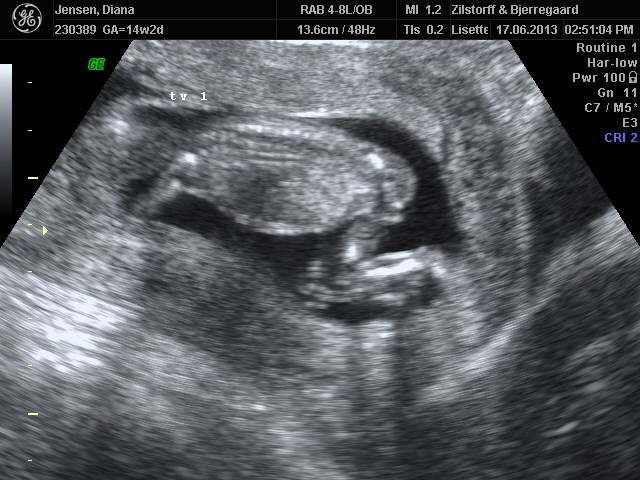

og self. kommer der lidt billeder

tvilling 1 først og tvillinge 2 næste og samme med mål